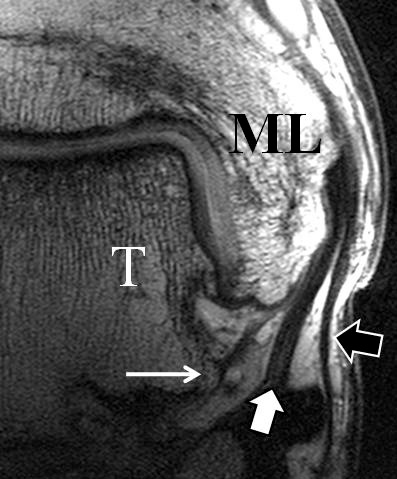

Zu Fehlinterpretationen eines intakten LFTA führt unter Umständen das unmittelbar kaudal des LFTA parallel verlaufende Ligamentum talocalcaneum laterale (Abb. 9 a). Dieses kann bei Verwendung von Schichtdicken um die 3 mm trotz Ruptur des LFTA durch Volumenteileffekte mit Anschnittsphänomenen einen intakten Bandverlauf vortäuschen.

Eine Ursache der falschen Diagnose einer LFTA-Ruptur ist die Fehlinterpretation der physiologische Bandlücke zwischen dem LFTA und der vorderen Syndesmose als traumatischer Banddefekt (Abb. 9 b).

Die Interpretation pathologischer Veränderungen sollte daher immer multiplanar unter Verwendung möglichst dünner Schichtdicken und hoher Ortsauflösungen erfolgen, um Fehldiagnosen zu vermeiden.